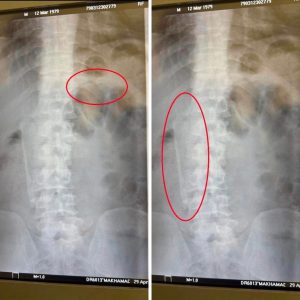

28- сәуір күні Кентау қаласында рентген жасалынып ине мен қасық жұттым деген азамат Мұхтар Сыздықовқа «рентген признаки инородного тела области толстой кишки справа» деп жазып берген.

Рентген суреттерінде жүрек тұсында инеге ұқсас темір зат және ішінде қасыққа ұқсас темір заттың тұрғанын байқауға болады. Ал дәрігердің жазбасында, «На обзорной рентгенограмме органов брюшной полости в прямой проекцииопределяются плотные тени в правой половине брюшной полости металлической плотности размером 14 см слева на уровне Th XI заднего отрезка размером 4 см»- деп жазып берген.